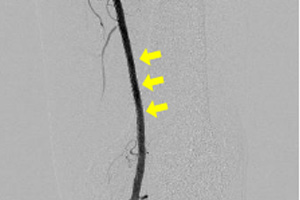

下肢動脈(浅大腿動脈)造影検査

ステント治療後